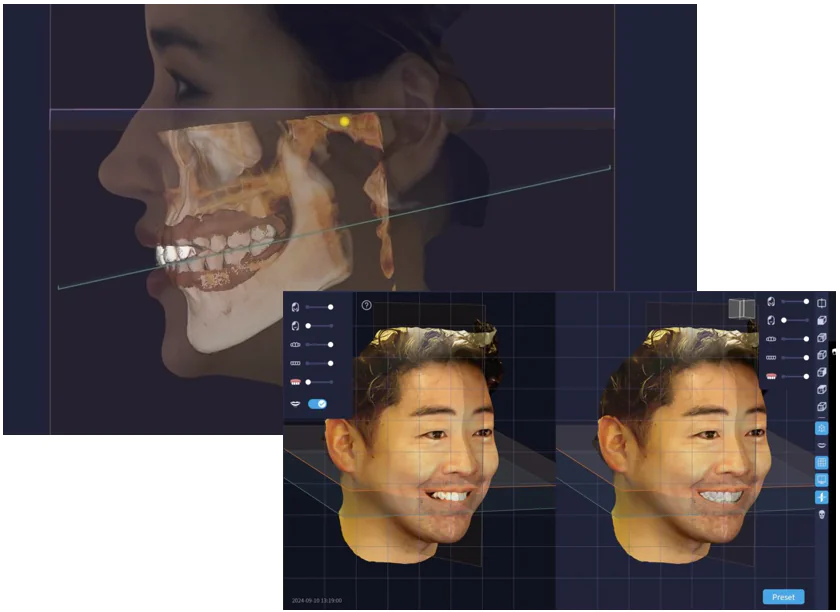

審美領域には最新の3次元的なデジタル診断

デジタルフェイススキャンを導入する事で、患者様の顔全体の骨格や歯並びをデータ化し高精度に解析でき、自然な見た目と噛み合わせを考慮したインプラント設計が可能になりました。また、従来の方法と比べて治療計画がより精密になり、手術のリスクを軽減する効果もあります。フェイススキャン技術を活用することで、患者様に最適なインプラント治療をご提供します。

デジタルフェイススキャンを導入する事で、患者様の顔全体の骨格や歯並びをデータ化し高精度に解析でき、自然な見た目と噛み合わせを考慮したインプラント設計が可能になりました。また、従来の方法と比べて治療計画がより精密になり、手術のリスクを軽減する効果もあります。フェイススキャン技術を活用することで、患者様に最適なインプラント治療をご提供します。